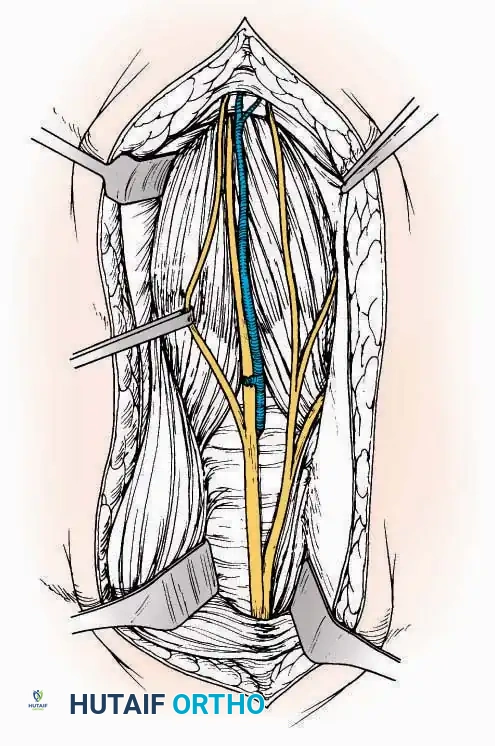

* Internervous Plane: The deep dissection exploits the plane between the Extensor Hallucis Longus (EHL) tendon (innervated by the deep peroneal nerve) and the Extensor Digitorum Longus (EDL) tendons (also innervated by the deep peroneal nerve).

* Neurovascular Bundle: Incise the extensor retinaculum. Carefully identify the anterior tibial artery and the deep peroneal nerve, which typically lie between the EHL and EDL, or directly deep to the EHL. Retract the neurovascular bundle laterally with the EDL, or medially with the EHL, depending on the specific anatomical variant encountered (lateral retraction is most common).

* Capsulotomy: Incise the anterior joint capsule longitudinally. Elevate the capsule subperiosteally from the anterior tibia and the talar neck to expose the entire tibiotalar articulation.